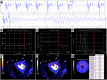

Case summary: We present a patient with coronary artery disease who developed an episode of ventricular fibrillation during a cardiovascular magnetic resonance examination. The arrhythmia appeared immediately after the injection of a contrast agent during a quantitative myocardial perfusion sequence at rest, with no stressor agent involved.

Discussion: To our knowledge, this is the first episode of ventricular fibrillation documented with simultaneous electrocardiographic, physiological recordings, and quantitative myocardial perfusion data. Such unique information allowed for a comprehensive analysis of the sequence of facts preceding the final arrhythmia and, in consequence, provided a well-reasoned conclusion on its mechanism.